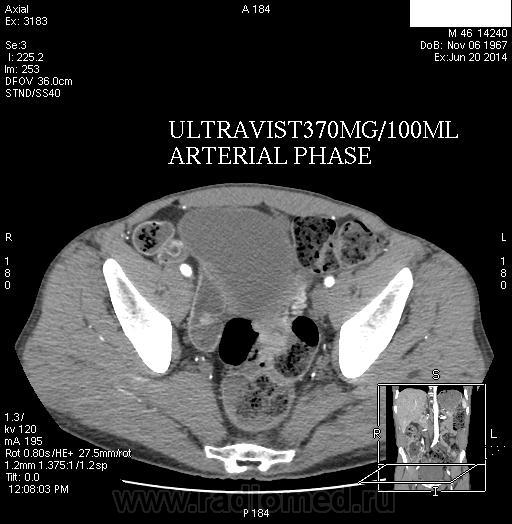

Напомню, пациент поступил с подозрением на ОНМК, на КТ выявлено V-образование в стволе мозга, написал с большей вероятностью mts. Клиницисты, увидев mts, молодцы насторожились и назначили УЗИ печени, а там очаги. Конечно, далее КТ ОБП+С. В печени гиповаскулярные mts. А первичное образование в ободочной кишке, при чем на разных уровнях локализации, в области печеночной кривизны, в ректосигмоидном отделе. Вероятно малигнизированные полипы. Клинические признаки кишечной непроходимости отсутствуют.